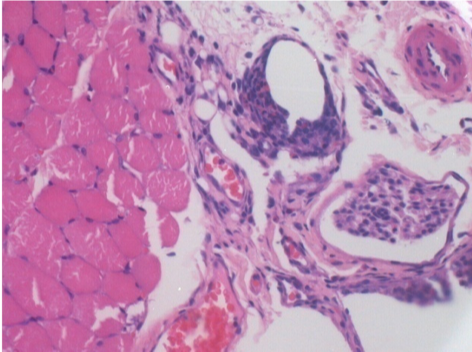

3 meses (D90) después de la inyección de Endopeel 0.1ml en el músculo pretibial derecho.

09

7 meses (D210) después de la inyección IM de Endopeel 0,1 ml en el músculo pretibial derecho.

Restitutio ad integrum (restauración a la condición original) completa después de 7 meses